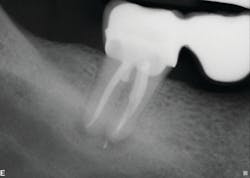

The second case involves a patient with tooth no. 19 having substantial furcation damage and moderate-sized apical periodontitis (figure 3).

Treatment included a two-visit approach, with two weeks in interim calcium hydroxide therapy.